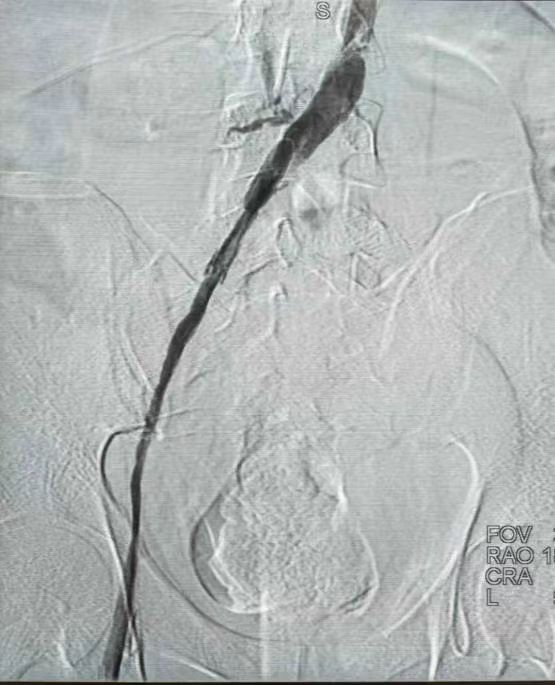

患者的血栓长达1米。

11日13时,胡育斌带领团队开始了“血管隧道里拆炸弹”的挑战之旅。他们身着厚重的铅衣,进入介入手术室。造影发现即使通过之前的药物溶栓治疗,左侧髂静脉及下腔静脉下段仍然有40厘米长的血栓完全堵塞,这条“血管隧道”被堵得严严实实。考虑继续药物治疗无法溶通,“白衣天团”只能凭着多年的经验和高超的介入微创医术“摸黑前行”。他们像“血管清道夫”般,在X射线的引导下,用导丝导管在“血管迷宫”中一寸寸“掘进”。

“光左髂静脉这一段20多厘米长的血栓,就打了1个多小时,下腔静脉这段10多厘米长的血栓,打了半个多小时。”而这半个多小时最惊心动魄,胡育斌顶着辐射贴身操作,在场医护人员纷纷被其精神所感染,“医者仁心”4个字在这一刻被具象化。最终,这场血管里的“毫米级微雕”历时3小时圆满成功,患者血流复通。